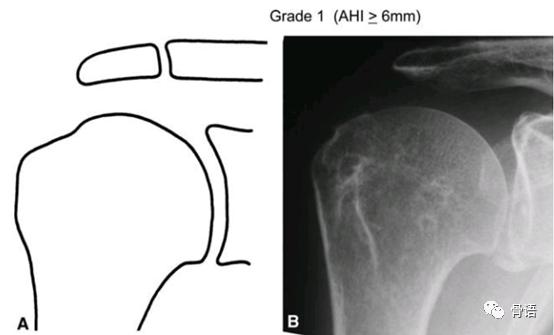

日本骨科医生东海大学浜田一寿(Kazutoshi Hamada)描述了巨大肩袖撕裂在X线上的影像学表现。Hamada分型对评估肩关节肩袖撕裂程度及骨性关节炎的程度具有重要的指导意义。可以指导我们是否需要进行肌腱转位手术或反式全肩关节置换术。

Grade1:肩峰和肱骨头之间的间隙≥6mm。